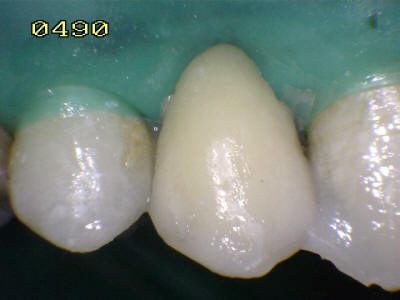

Aislación absoluta con dique de goma

Grabado con ácido ortofosfórico

Flechas rojas: Esmalte grabado   Flechas azul resina compuesta

Cementado con la goma dique.  Observe los excesos de cemento de resina de curado dual (flechas blancas)